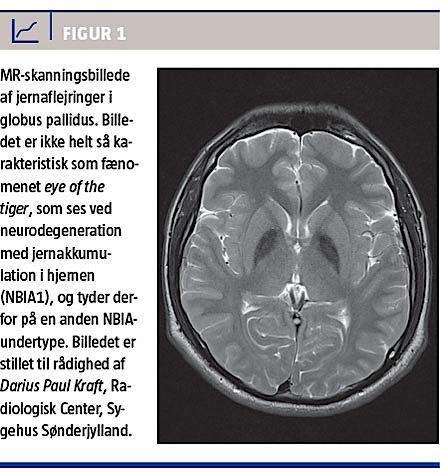

Neurodegeneration med jernakkumulation i hjernen (neurodegeneration with brain iron accumulation, NBIA) er en heterogen gruppe af overvejende autosomal recessivt arvelige sygdomme, som er karakteriseret ved progressive motoriske og kognitive problemer. Symptomerne debuterer i barndommen eller den tidlige voksenalder. De motoriske symptomer er bl.a. nedsat kraft, spasticitet, dysartri og dystoni. De kliniske symptomer omfatter også andre dele af nervesystemet inkl. opticusatrofi. Klinikerens vej til diagnosen for denne sygdomsgruppe vil typisk være det specifikt abnorme resultat af MR-skanninger, der viser jernaflejringer i basalganglierne. MR-skanningsfundet kan forudgå de kliniske symptomer. Helt klassisk ses der ved T2-vægtet skanning hypodensitet symmetrisk i globi pallidi evt. med central fortætning som eye of the tiger (Figur 1).

Ved gentagen udredning fandt man normale forhold ved metaboliske analyser, array-komparativ genomisk hybridisering og undersøgelse for dystrophia myotonica. Ved en øjenlægeundersøgelse bekræftedes aftagende visus (0,24/0,4). En oftalmoskopi viste opticusatrofi. En MR-skanning af cere-

brum viste symmetriske hypodensiteter med central fortætning i globus pallidus og substantia nigra (Figur 1). Genetisk undersøgelse kunne bekræfte NBIA4/MPAN (mutationen c.204_214del11 i homozygot form i genet C19orf12, der koder for et mitokondriemembranprotein). En lillesøster med lignende symptomer fik siden påvist den samme homozygote mutation.